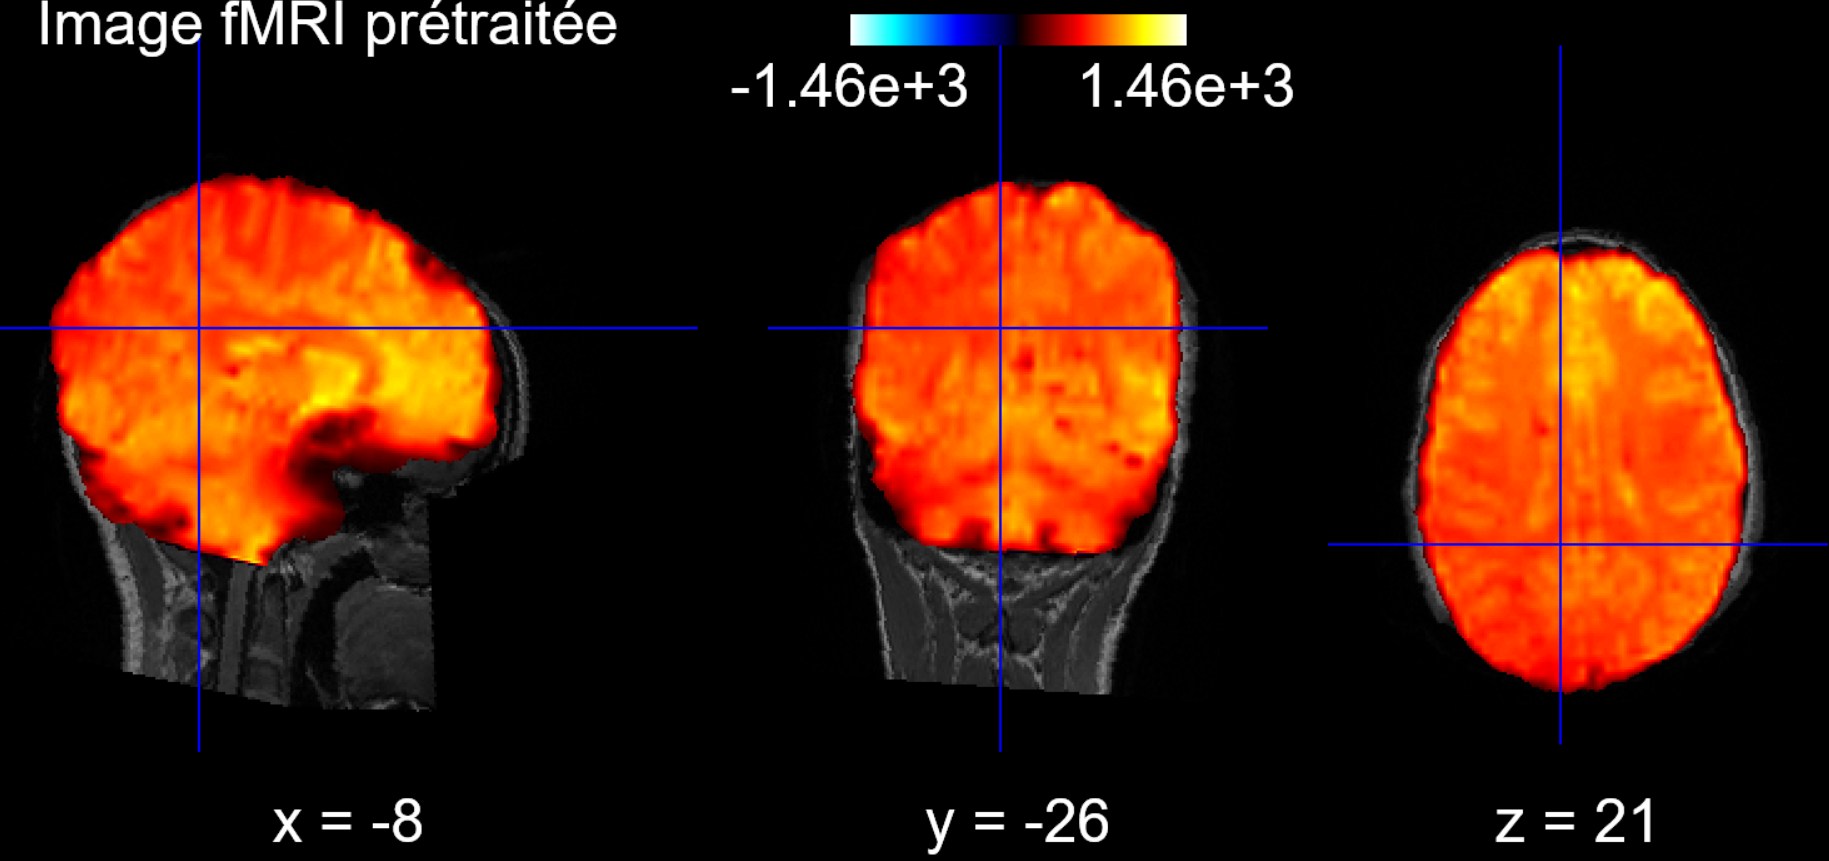

2.1 Brain Preprocessing

First, we extract the brain from the fMRI data to keep only the exploitable part:

Second, we align the brain to the corresponding T1 scan of the patient to be able to apply an atlas later: